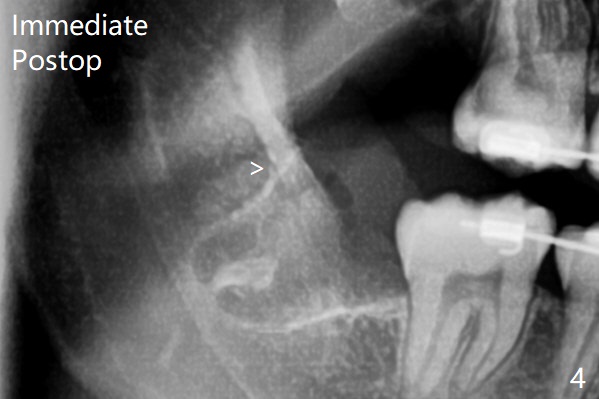

14岁外斜嵴尚未完全形成(图一:箭头);17岁时外斜嵴近中部分仍然被智齿阻挡而没有形成或者去除颊侧骨板时失去(图四),但是密度增加。这两个智齿不位于第二磨牙颊侧。